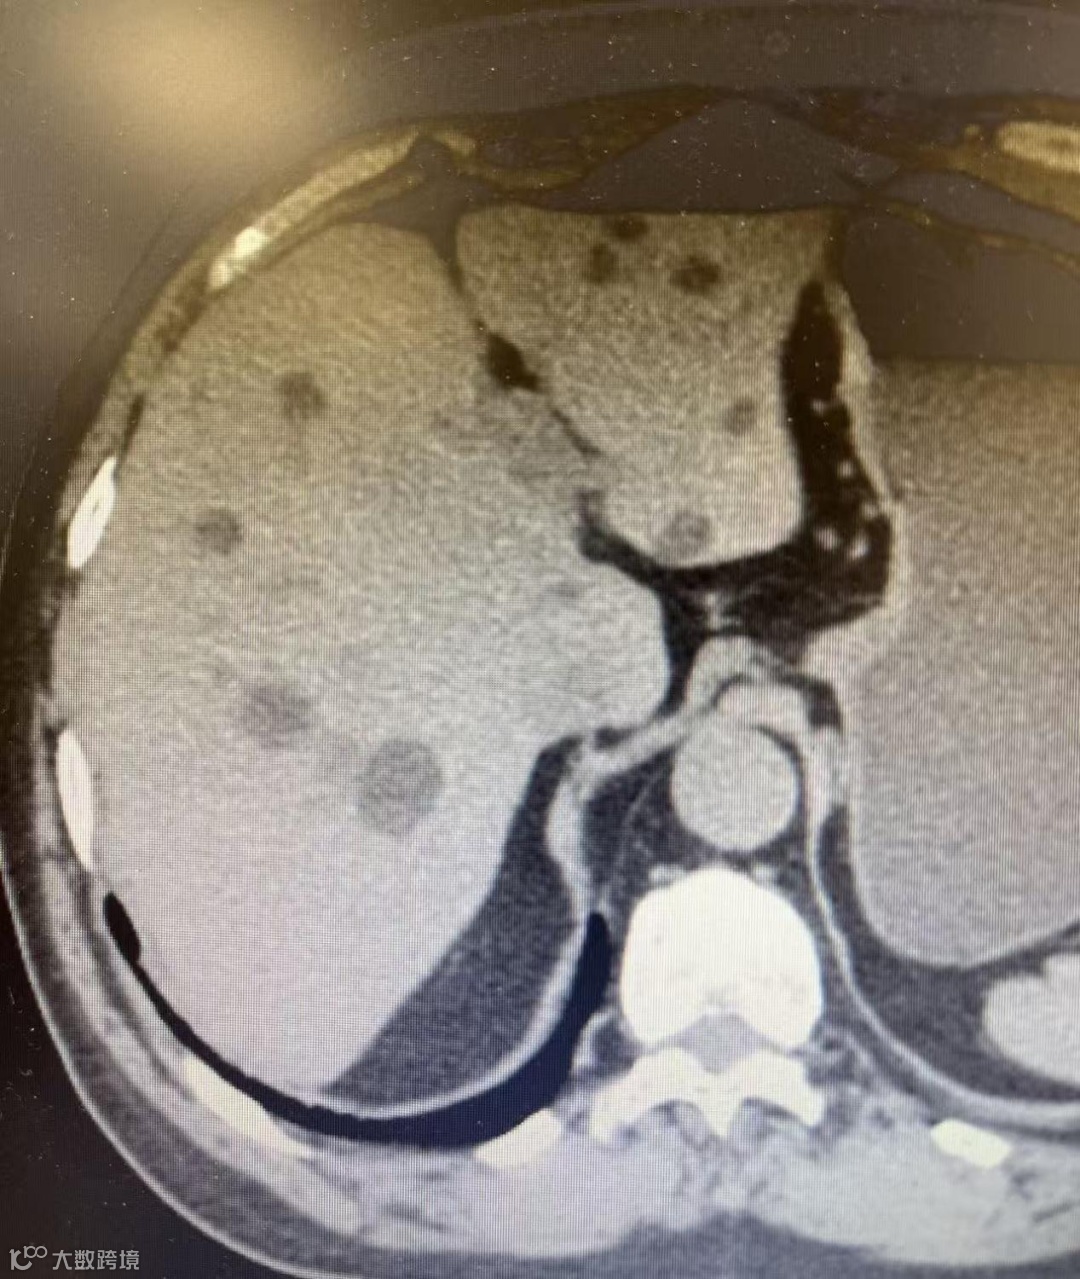

近日,我院呼吸介入团队在有着数十年介入诊疗经验的科室业务主任成佳科带领下,成功为一名体检发现多发肝囊肿的患者实施了CT引导下肝囊肿穿刺聚桂醇硬化治疗术。手术全程严格遵循《多脏器囊肿硬化治疗中国专家共识》规范,患者术后恢复平稳,标志着我院介入技术在跨病种治疗上稳定发挥。

肝囊肿是临床最常见的肝脏良性囊性病变之一,人群患病率约为2.5%~18%,多数为单纯性肝囊肿,囊内为清亮液体,囊壁薄且均匀。

需要注意的是,复杂性囊肿需结合超声造影、CT、MRI及肿瘤标志物,必要时穿刺活检以排除恶性病变。

术前,科室团队结合患者影像资料进行了细致评估,精准规划了穿刺路径。术中在CT实时引导下,穿刺针准确抵达目标位置,成功抽吸囊液并完成冲洗。随后,经造影确认位置无误后,注入硬化剂并保留。术后复查显示囊肿已基本消失,手术取得预期效果。整个流程平稳有序,以微创方式为患者解除了病痛。